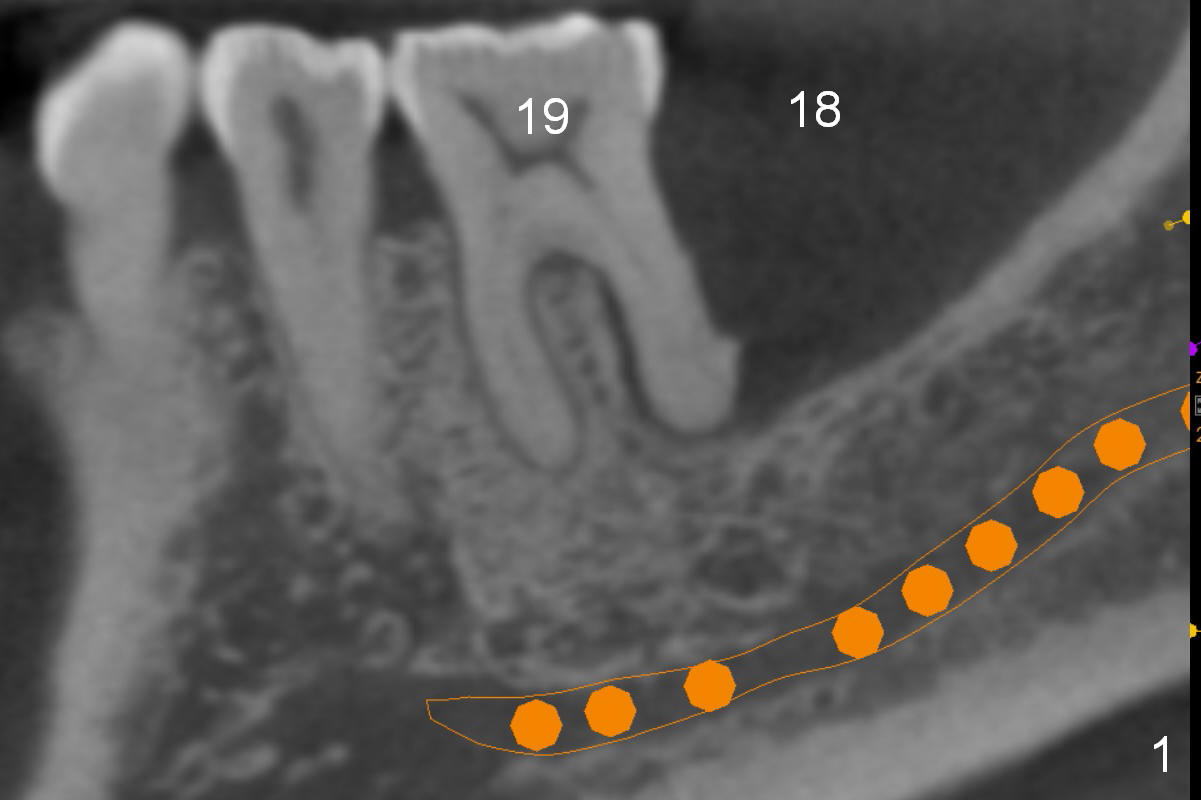

There is severe bone resorption around the distal root of the lower left 1st molar of the 56-year-old man (WG), while the loss of the 2nd molar is associated with limited bone height (Fig.1). A 5x14 mm implant will be placed at the mesial socket of #19 and 5.9 or 6.4x6 mm one is at the mesial site of #18 (Fig.7-9). Use a 2 mm pilot drill with 6 mm stopper from Sinus Master Kit (with extension) to initiate osteotomy at #18 immediately distal to the crown of #19, parallel to the long axis of the latter (Fig.2). After inserting a parallel pin at #18, extract the tooth #19 (Fig.3, antibiotic pending) and start osteotomy with a 2 mm pilot drill with 14 mm stopper (Fig.4). Insert the calibrated parallel pin at #19 (Fig.5) and measure the distance between the two parallel pins (approximately 10 mm, Fig.7). Sequential osteotomy and application of the Tatum taps (Fig.6 red rectangle) will push the septum distal (green arrow). As to #18 osteotomy, trephine, final and tap drills are to be used with control of the depth: 6 mm (Fig.7,9).